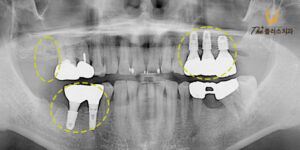

대합되는 하악 대구치의 경우에도

상태가 좋지 않았는데요.

마찬가지로 맨 안쪽 대구치 주변으로는 잇몸이 부어있고,

염증으로 인해 치조골이 퇴축되어 연결된 브릿지

전체가 흔들리고 있었습니다.

파노라마 사진상으로는 보철물 속의

내부를 알 수 없기 때문에

브릿지를 제거해본 후 소구치의 상태를 파악하여

재 크라운이나 임플란트를 진행하기로 하였습니다.

어느 정도 아물고 난 후

상악 대구치를 발치 하였으며,

아래쪽 하악 브릿지를 제거하고 보니 소구치의 내부도

상태가 좋지 않아 함께 발치 후 위,

아래 교합이 맞도록 큰 어금니 하나를 제외하고

임플란트를 식립하였습니다.

양쪽 모두 임플란트와 치조골이

단단히 유착한 것을 확인하고 보철물을 제작하였고,